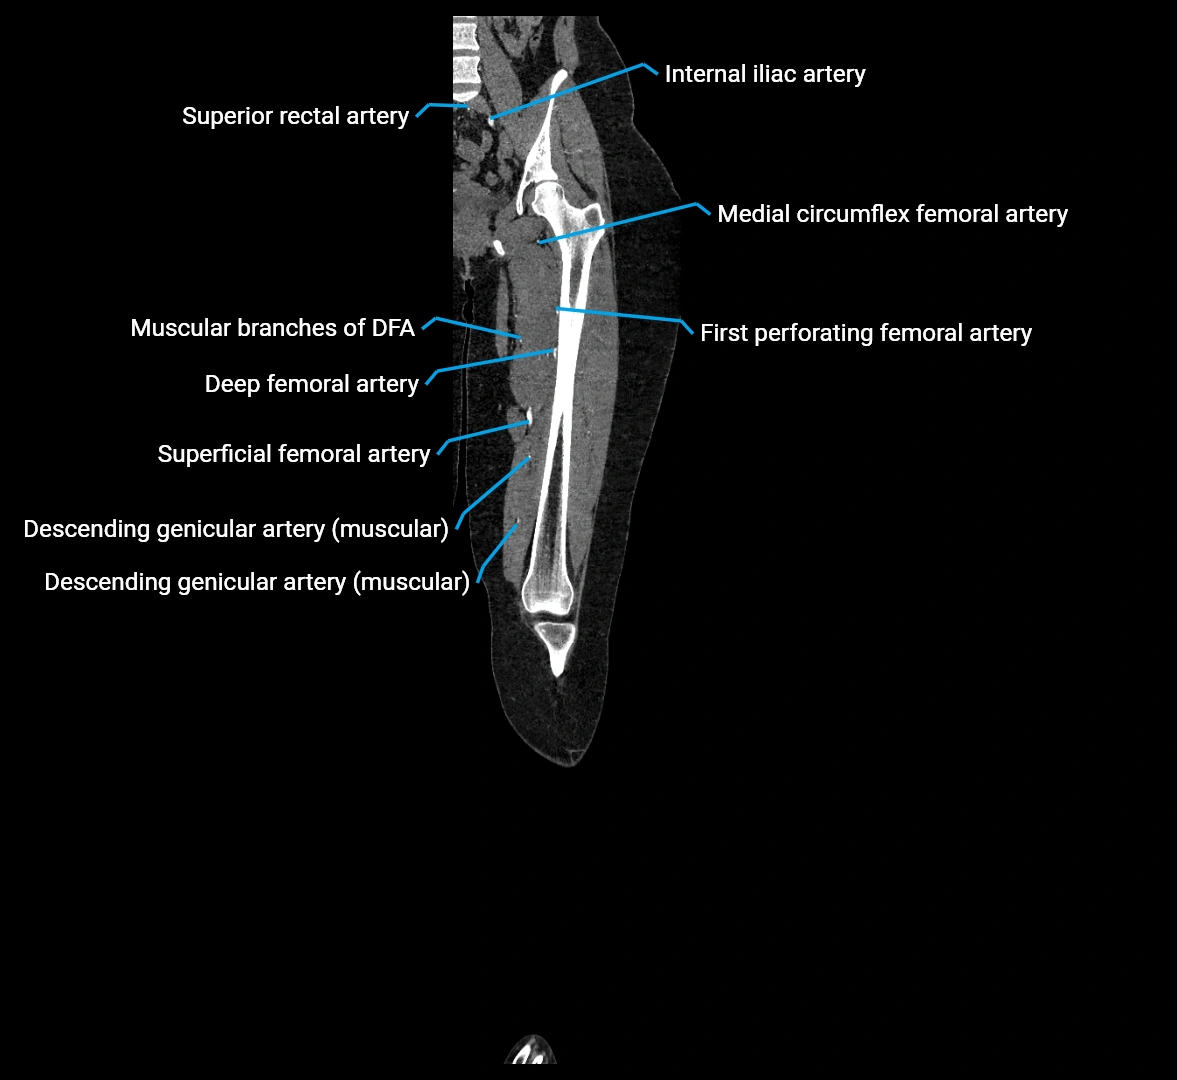

Branches

• Unpaired visceral branches: celiac trunk, superior mesenteric artery (SMA), inferior mesenteric artery (IMA)

• Paired visceral branches: middle suprarenal arteries, renal arteries, gonadal arteries (testicular or ovarian)

• Parietal branches: inferior phrenic arteries, lumbar arteries, median sacral artery

• Terminal branches: right and left common iliac arteries

Contrast-enhanced CT (CTA):

• Gold standard for abdominal aortic imaging

• Provides excellent detail of lumen, wall, aneurysm, thrombus, and branch vessels

• Multiplanar and 3D reconstructions help in aneurysm measurement, stent graft planning, and dissection evaluation

• Detects acute rupture, traumatic injury, or occlusion with high sensitivity